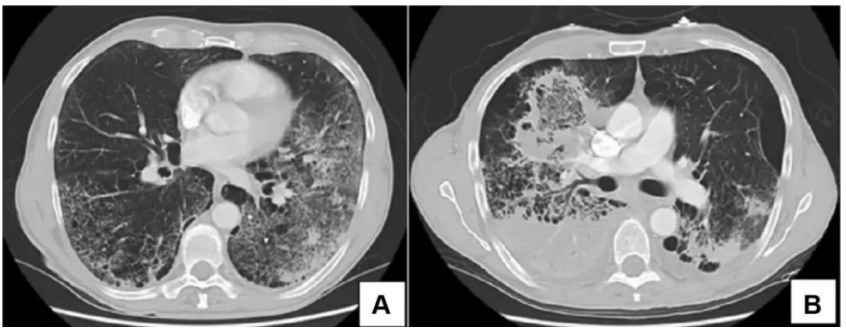

患者男性,51岁,因“咳嗽、咳痰5天,发热伴呼吸困难3天”入院。入院前曾应用静脉激素。既往有胰腺癌病史,入院后发现血糖明显升高,并确诊2型糖尿病。乙型流感病毒核酸阳性。血清GM试验阴性,BALF GM >5 S/CO,曲霉IgG阴性,BALF mNGS提示烟曲霉(序列数809975),乙型流感病毒(序列数2732),BALF培养结果为烟曲霉,对伏立康唑耐药。患者胸部CT及气管镜结果如下图所示。患者,男性,36岁,因“咳嗽、咳痰1周,呼吸困难2天”入院。入院前2天外院诊断糖尿病酮症酸中毒、乙型流感病毒性肺炎,并有使用静脉激素。入院查乙型流感病毒核酸阳性。BALF GM>5 S/CO,血清GM 4.8 S/CO,曲霉IgG阴性,BALF mNGS提示烟曲霉(序列数25173),乙型流感病毒(序列数90),气道假膜钳夹组织及BALF培养烟曲霉。患者胸部CT及气管镜结果如下图所示。IAPA的发病率较高,且在不同的流感亚型中无显著差异。而且IAPA的病死率高,但早期临床表现缺乏特异性,诊断存在一定困难,应引起临床医师的高度关注。早期、准确地识别与诊断IAPA,及时启动抗真菌治疗是改善预后的关键。[1] Iuliano AD, Roguski KM, Chang HH, et al. Estimates of global seasonal influenza‑associated respiratory mortality: a modelling study[J]. Lancet, 2018, 391(10127):1285-1300. [2] Verweij PE, Rijnders BJA, Brüggemann RJM, et al. Review of influenza‑associated pulmonary aspergillosis in ICU patients and proposal for a case definition: an expert opinion[J]. Intensive Care Med, 2020, 46(8): 1524-1535.[3] Martin-Loeches I, J Schultz M, Vincent JL, et al. Increased incidence of co-infection in critically ill patients with influenza[J]. Intensive Care Med, 2017, 43(1):48-58.[4] ABBOTT JD, FERNANDO HV, GURLING K, et al. Pulmonary aspergillosis following post‑influenzal bronchopneumonia treated with antibiotics[J]. Br Med J, 1952, 1(4757):523-525. [5] Martin-Loeches I, J Schultz M, Vincent JL, et al. Increased incidence of coinfection in critically ill patients with influenza[J]. Intensive Care Med, 2017, 43:48-58.[6] Schauwvlieghe AFAD, Rijnders BJA, Philips N, et al. Invasive aspergillosis in patients admitted to the intensive care unit with severe influenza: a retrospective cohort study[J]. Lancet Respir Med, 2018, 6(10): 782-792.[7] Beumer MC, Koch RM, van Beuningen D, et al. Influenza virus and factors that are associated with ICU admission, pulmonary co-infections and ICU mortality[J]. J Crit Care, 2019, 50:59-65. [8] Huang L, Zhang N, Huang X, et al. Invasive pulmonary aspergillosis in patients with influenza infection: a retrospective study and review of the literature[J]. Clin Respir J, 2019, 13(4):202-211. [9] Krifors A, Blennow O, Påhlman LI, et al. Influenza-associated invasive aspergillosis in patients admitted to the intensive care unit in Sweden: a prospective multicentre cohort study[J]. Infect Dis (Lond), 2024, 56(2):110-115.[10] Lu LY, Lee HM, Burke A, et al. Prevalence, Risk Factors, Clinical Features, and Outcome of Influenza-Associated Pulmonary Aspergillosis in Critically Ill Patients: A Systematic Review and Meta-Analysis[J]. Chest, 2024, 165(3):540-558. [11] Delaney JW, Pinto R, Long J, Lamontagne F, et al. The influence of corticosteroid treatment on the outcome of influenza A (H1N1pdm09)‑related critical illness[J]. Crit Care, 2016, 20:75.[12] [Nedel WL, Nora DG, Salluh JI, et al. Corticosteroids for severe influenza pneumonia: A critical appraisal[J]. World J Crit Care Med, 2016, 5(1):89-95.[13] Wauters J, Baar I, Meersseman P, et al. Invasivepulmonary aspergillosis is a frequent complication of critically ill H1N1 patients: a retrospective study[J]. Intensive Care Med, 2012, 38(11):1761-1768.[14] Rodriguez-Goncer I, Thomas S, Foden P, et al. Invasive pulmonary aspergillosis is associated with adverse clinical outcomes in critically ill patients receiving veno‑venous extracorporeal membrane oxygenation[J]. Eur J Clin Microbiol Infect Dis, 2018, 37(7):1251-1257. [15] Cavayas YA, Yusuff H, Porter R. Fungal infections in adult patients on extracorporeal life support[J]. Crit Care, 2018, 22(1):98. [16] Clancy CJ, Nguyen MH. Acute community-acquired pneumonia due to Aspergillus in presumably immunocompetent hosts: clues for recognition of a rare but fatal disease[J]. Chest, 1998, 114:629-634.[17] Hasejima N, Yamato K, Takezawa S, et al. Invasive pulmonary aspergillosis associated with influenza B[J]. Respirology, 2005;10:116-119.[18] van de Sandt CE, Bodewes R, Rimmelzwaan GF, et al, Rimmelzwaan GF, de Vries RD. Influenza B viruses: not to be discounted[J]. Future Microbiol, 2015, 10(9):1447-1465. [19] Matias G, Taylor R, Haguinet F, et al. Estimates of mortality attributable to influenza and RSV in the United States during 1997-2009 by influenza type or subtype, age, cause of death, and risk status[J]. Influenza Other Respir Viruses, 2014, 8(5):507-515.[20] Kuek LE, Lee RJ. First contact: the role of respiratory cilia in host-pathogen interactions in the airways[J]. Am J Physiol Lung Cell Mol Physiol, 2020, 319(4):L603-L619.[21] Ghoneim HE, Thomas PG, McCullers JA. Depletion of alveolar macrophages during influenza infection facilitates bacterial superinfections[J]. J Immunol, 2013, 191(3):1250-1259.[22] Fox A, Le NM, Horby P, et al. Severe pandemic H1N1 2009 infection is associated with transient NK and T deficiency and aberrant CD8 responses[J]. PLoS One, 2012, 7(2):e31535.[23] Short KR, et al. Pathogenesis of influenza induced acute respiratory distress syndrome. Lancet Infect Dis. 2014;14(1): 57-69.[24] Dewi IM, et al. Neuraminidase and SIGLEC15 modulate the host defense against pulmonary aspergillosis. Cell Rep Med. 2021;2(5): 100289.[25] Ohta H, Yamazaki S, Miura Y, et al. Invasive tracheobronchial aspergillosis progressing from bronchial to diffuse lung parenchymal lesions[J]. Respirol Case Rep, 2016, 4(1):32-34.[26] Saha BK, Chong W. A 61-Year-Old Man With Influenza Pneumonia and New Onset Hemoptysis[J]. Chest, 2021, 160(2):e181-e184.[27] 罗丹心, 谷林, 阎锡新. 体外膜肺氧合治疗重症流感相关肺曲霉病1例并文献复习[J]. 国际呼吸杂志, 2023, 43(4):448-453.[28] Park DW, Yhi JY, Koo G, et al. Fatal clinical course of probable invasive pulmonary aspergillosis with influenza B infection in an immunocompetent patient[J]. Tuberc Respir Dis (Seoul), 2014, 77(3):141-144.[29] Meersseman W, Vandecasteele SJ, Wilmer A, et al. Invasive aspergillosis in critically ill patients without malignancy[J]. Am J Respir Crit Care Med, 2004, 170(6):621-625.[30] Lahmer T, Neuenhahn M, Held J, et al. Comparison of 1,3-β-dglucan with galactomannan in serum and bronchoalveolar fluid for the detection of Aspergillus species in immunosuppressed mechanical ventilated critically ill patients[J]. J Crit Care, 2016, 36:259-264.[31] Zhu N, Zhou D, Xiong W, et al. Performance of mNGS in bronchoalveolar lavage fluid for the diagnosis of invasive pulmonary aspergillosis in non-neutropenic patients[J]. Front Cell Infect Microbiol, 2023, 13:1271853.[32] Patterson TF, Thompson GR 3rd, Denning DW, et al. Practice Guidelines for the Diagnosis and Management of Aspergillosis: 2016 Update by the Infectious Diseases Society of America[J]. Clin Infect Dis, 2016, 63(4):e1-e60. [33] Ullmann AJ, Aguado JM, Arikan-Akdagli S, et al. Diagnosis and management of Aspergillus diseases: executive summary of the 2017 ESCMID-ECMM-ERS guideline[J]. Clin Microbiol Infect, 2018, 24 Suppl 1:e1-e38. [34] Lu Y, Liu L, Li H, et al. The clinical value of Aspergillus-specific IgG antibody test in the diagnosis of nonneutropenic invasive pulmonary aspergillosis[J]. Clin Microbiol Infect, 2023, 29(6):797.e1-797.e7. [35] Donnelly JP, Chen SC, Kauffman CA, et al. Revision and Update of the Consensus Definitions of Invasive Fungal Disease From the European Organization for Research and Treatment of Cancer and the Mycoses Study Group Education and Research Consortium[J]. Clin Infect Dis, 2020, 71(6):1367-1376.[36] Springer J, White PL, Hamilton S, et al. Comparison of performance characteristics of Aspergillus PCR in testing a range of blood-based samples in accordance with international methodological recommendations[J]. J Clin Microbiol, 2016, 54(3):705-711.[37] Eigl S, Hoenigl M, Spiess B, et al. Galactomannan testing and Aspergillus PCR in same-day bronchoalveolar lavage and blood samples for diagnosis of invasive aspergillosis[J]. Med Mycol, 2017, 55(5):528-534.[38] Mengoli C, Cruciani M, Barnes RA, et al. Use of PCR for diagnosis of invasive aspergillosis: systematic review and meta-analysis[J]. Lancet Infect Dis, 2009, 9(2):89-96.[39] Springer J, Lackner M, Nachbaur D, et al. Prospective multicentre PCR-based Aspergillus DNA screening in high-risk patients with and without primary antifungal mould prophylaxis[J]. Clin Microbiol Infect, 2016, 22(1):80-86.[40] 施毅, 赵江南. 侵袭性真菌病病原学非培养实验室诊断方法[J]. 中华结核和呼吸杂志, 2019, 42(7):500-505[41] Eigl S, Prattes J, Lackner M, et al. Multicenter evaluation of a lateral-flow device test for diagnosing invasive pulmonary aspergillosis in ICU patients[J]. Crit Care, 2015, 19(1):178.[42] Jenks JD, Mehta SR, Taplitz R, et al. Point-of-care diagnosis of invasive aspergillosis in non-neutropenic patients: aspergillus galactomannan lateral flow assay versus aspergillus-specific lateral flow device test in bronchoalveolar lavage[J]. Mycoses, 2019, 62(3):230-236.[43] Maertens JA, Raad II, Marr KA, et al. Isavuconazole versus voriconazole for primary treatment of invasive mould disease caused by Aspergillus and other filamentous fungi (SECURE): a phase 3, randomised-controlled, non-inferiority trial[J]. Lancet, 2016, 387(10020):760-769.[44] Maertens JA, Rahav G, Lee DG, et al. Posaconazole versus voriconazole for primary treatment of invasive aspergillosis: a phase 3, randomised, controlled, non-inferiority trial[J]. The Lancet, 2021, 397(10273):499-509.[45] Thompson 3rd GR, Soriano A, Cornely OA, et al. Rezafungin versus caspofungin for treatment of candidaemia and invasive candidiasis (ReSTORE): a multicentre, double-blind, double-dummy, randomised phase 3 trial[J]. Lancet, 2023, 401(10370):49-59.[46] Shaw KJ, Ibrahim AS. Fosmanogepix: A Review of the First-in-Class Broad Spectrum Agent for the Treatment of Invasive Fungal Infections[j]. J Fungi (Basel), 2020, 6(4):239. [47] Petraitis V, Petraitiene R, Katragkou A, et al. Combination Therapy with Ibrexafungerp (Formerly SCY-078), a First-in-Class Triterpenoid Inhibitor of (1→3)-β-d-Glucan Synthesis, and Isavuconazole for Treatment of Experimental Invasive Pulmonary Aspergillosis[J]. Antimicrob Agents Chemother, 2020, 64(6):e02429-19.[48] Wiederhold NP. Review of the Novel Investigational Antifungal Olorofim[J]. J Fungi (Basel), 2020, 6(3):122. [49] Zhou M, Liu L, Cong Z, et al. A dual-targeting antifungal is effective against multidrug-resistant human fungal pathogens[J]. Nat Microbiol, 2024, 9(5):1325-1339.